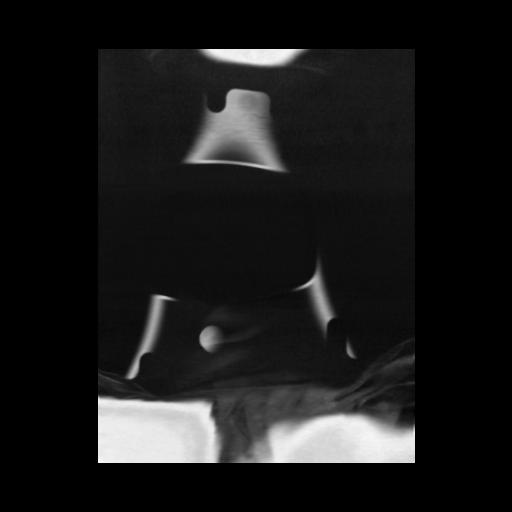

13 P.BLANDAS,,Coronal,2.000,P.BLANDAS,Coronal,